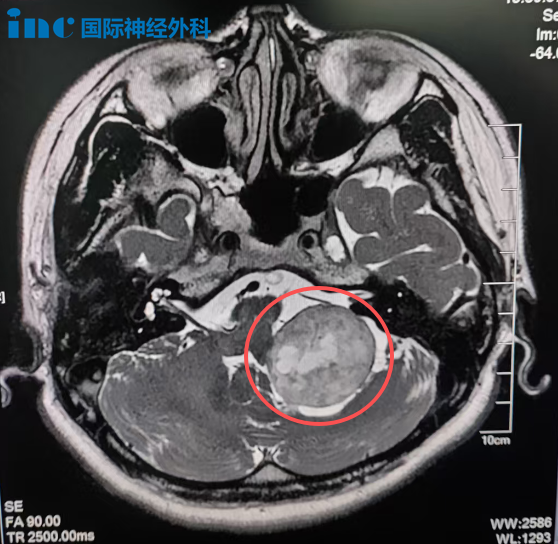

2023年底一次意外摔倒后检查发现左侧桥小脑角区存在约36×32mm占位病变。由于位置深在、毗邻重要神经血管,手术被评估为高风险。患者不得已选择射波刀放疗,期望以较小代价控制病情。

在朋友推荐下,林女士找到巴教授。从咨询到手术仅用一个月时间。巴教授详细研究影像资料后指出:病变位于左侧桥小脑角区,累及颈静脉孔,形态学表现符合后组颅神经来源的神经鞘瘤,但不能排除其他肿瘤类型。手术切除是明确可行的治疗方案。

最终,这台由巴教授主刀的高难度手术在苏州大学附属第四医院成功完成,肿瘤达到满意切除。术后病理检查结果与巴教授术前评估一致,确诊为神经鞘瘤。